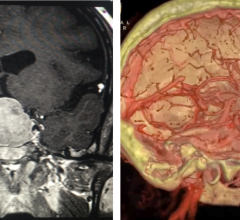

iSchemaView announced the release of RAPID Angio, a complete neuroimaging solution for the angiography suite that integrates iSchemaView’s RAPID software with syngo DynaCT Multiphase from Siemens Healthineers. The syngo DynaCT Multiphase is a three-dimensional image acquisition technique employing multiple rotations of a C-arm system to acquire a multi-phasic 3-D representation of the brain and its perfusion. This technology, when combined with the RAPID platform’s CTP product, delivers a powerful imaging solution to the angio suite for acute stroke patients.